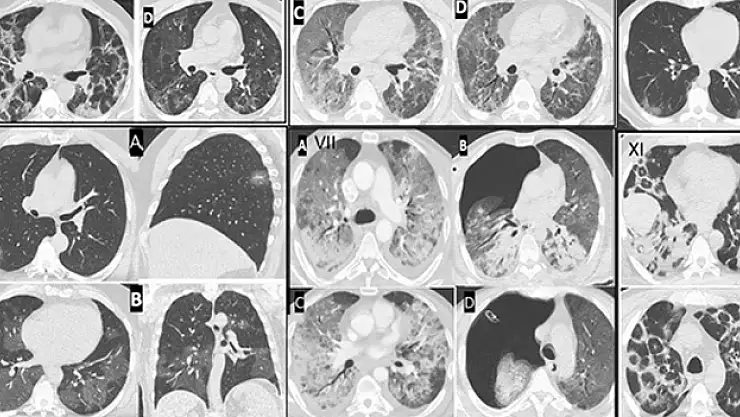

Prof. Dr. Şevket Özkaya, Göğüs Hastalıkları Anabilim Dalı öğretim üyelerinin dahil olduğu 12 bine yakın COVID -19 hastasının incelendiği önemli klinik çalışma yapıldığını belirtti. Bu araştırmanın sonuçlarına göre COVID-19 virüsü ile enfekte kişilerde ve özellikle akciğer tutulumu olanlarda endotel hasarının görüldüğünün saptandığına işaret etti. Özkaya, özellikle pandemi ile damar hasarı ve tıkanıklıkların genç yaşlara inmesinin COVID salgını mı yoksa aşıların mı neden olduğu sorusunun ise hem tıp camiasında hem de toplumda tartışmaları devam ettiğini söyledi.